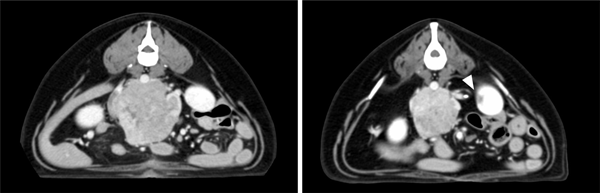

The lesion was diagnosed as a right adrenal tumour. Ultrasonographic examination showed invasion into the surrounding tissue and the CVC, while thoracic radiographs ruled out pulmonary metastasis. Based on the WHO classification, the tumour was graded as T3N0M0. A CT examination performed on day 6 (figure 1, left) showed that the tumour measured 88 × 76 × 75 mm and had pushed the right kidney caudally. An intraoperative core biopsy was performed by laparotomy, followed by radiation therapy. The radiotherapy regimen included 23.7 Gy/three fractions/three weeks, and 95 per cent of the tumour received 7.9 Gy (figure 2). The right kidney over 4 Gy was only 26 per cent, and the intestine over 8 Gy was 1.1 ml in one fraction. Pathological examination of the tumour indicated an adenocarcinoma. Four months after treatment, the tumour size reduced to 66 × 61 × 42 mm, and the tumour volume was down to 34 per cent of the initial volume (figure 1, right), and this reduction was maintained for 11 months. There were no clinical radiation toxicities, including changes in renal size, and blood chemistry (before radiotherapy: alanine aminotransferase (ALT) 50 iu/l (reference range: 18–71), blood urea nitrogen (BUN) 11.6 mg/dl (reference range: 15–37) and Crea 0.6 mg/dl (reference range: 0.8–1.8), one month later: ALT 37 iu/l, BUN 11.0 mg/dl and Crea 0.6 mg/dl, and two years later: ALT 62 iu/dl, BUN 44.7 mg/dl and Crea 0.8 mg/dl). Hepatic changes around the CVC could be detected in the CT image (figure 1, right). However, adverse events based on VRTOG and VCOG‐CTCAE were not detected. Fifteen months after treatment, the tumour showed a gradual increase in size, with an invasion of the spine. Lung metastasis was detected 25 months later. The survival time, in this case, was 27 months after the last round of radiation therapy.

Figure 1

CT images of the adrenal tumour in case 1. An axial image on day 1 of radiotherapy (left). An axial image at eight months after the initial treatment (right) shows a reduction in the tumour size and changes in the adjacent liver (arrowhead).